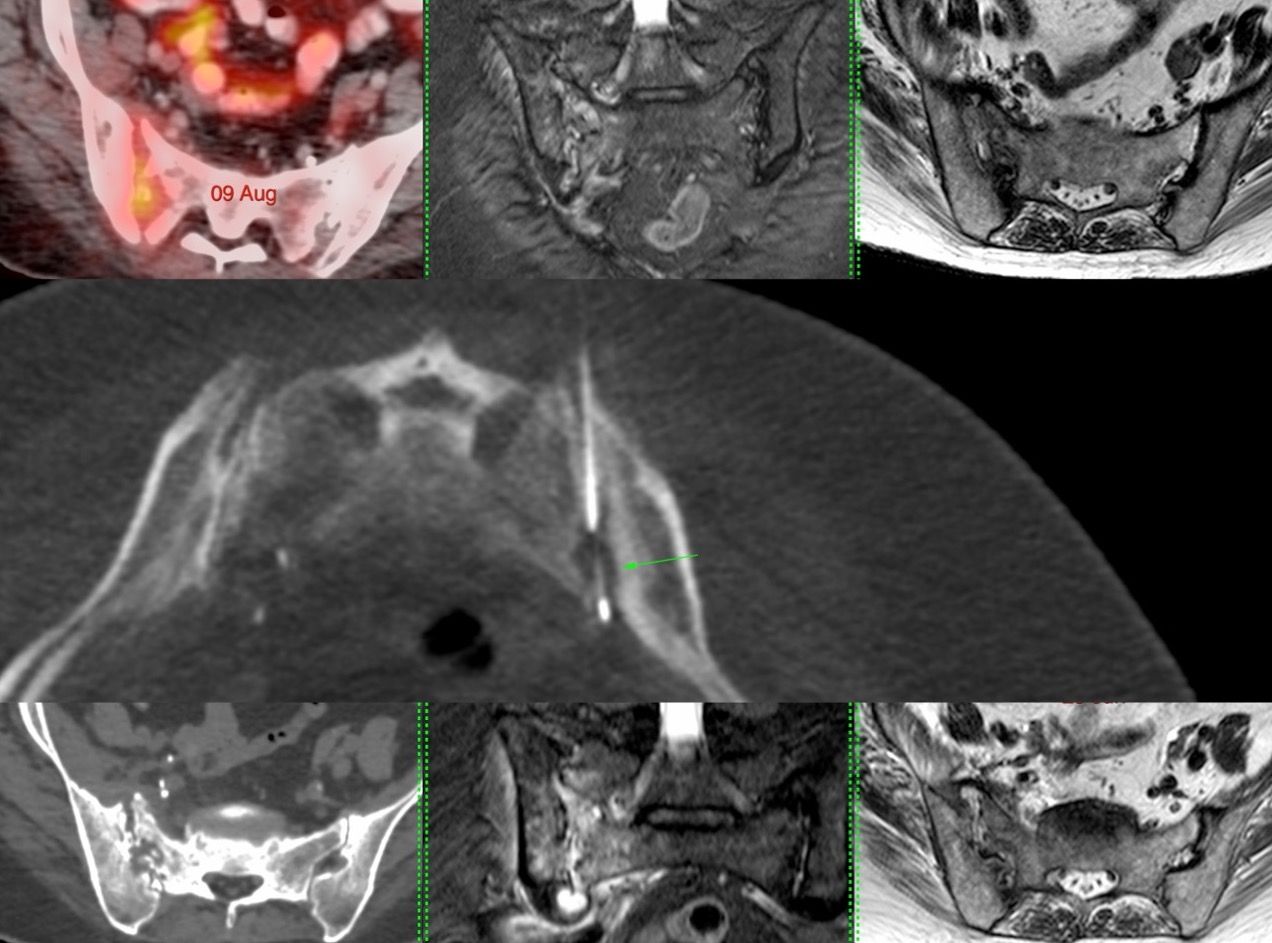

Case 100: Gallbladder Mass Biopsy

Bhavin Jankharia - 09 August 2022